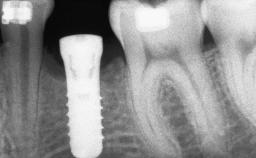

A 56-year-old woman presented for treatment with complete edentulism of the maxilla. She had been using a complete removable denture since she was relatively young (age 30). Her chief complaint at presentation was lack of retention of the upper denture and a desire for a better restoration in order to improve retention, function, and esthetics. An initial clinical examination showed that the anterior maxilla was moderately atrophic both horizontally and vertically, also revealing a vertical deficiency of the posterior alveolar process. The mandible included natural teeth from 45 to 35, with previous extrusion of the anterior teeth that was being orthodontically treated. Also, there were two external hexagon dental implants at sites 46 and 36 that had been inserted elsewhere at a previous point in time. As the conditions in the mandible were healthy, including the teeth and the two implants, the patient had no complaints there.

# of Implants | 8 |

Type of Implants | One-Piece |